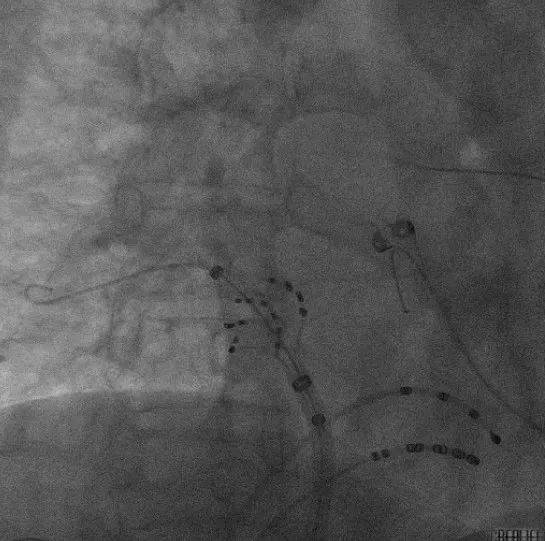

ICE引导下房间隔穿刺:

术中ICE指引导丝到上腔静脉

ICE直视下进行房间隔穿刺

穿刺后打水确认